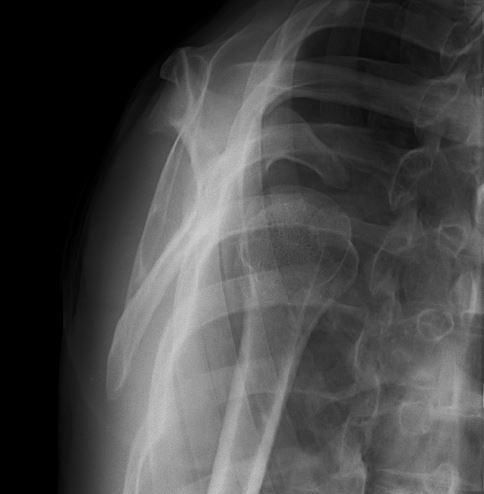

単純レントゲン画像

正面

上腕骨が前方に脱臼

Yビュー